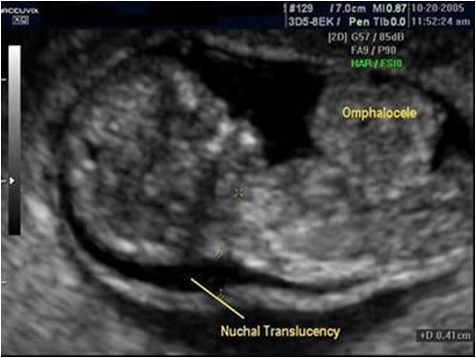

【产前诊断(Prenatal diagnosis)】

胎儿超声与MRI:可见胎儿胸腔内有腹部脏器

◇产前诊断

B超 腹壁呈肿瘤样突出→有包膜为脐膨出

→无包膜为腹裂